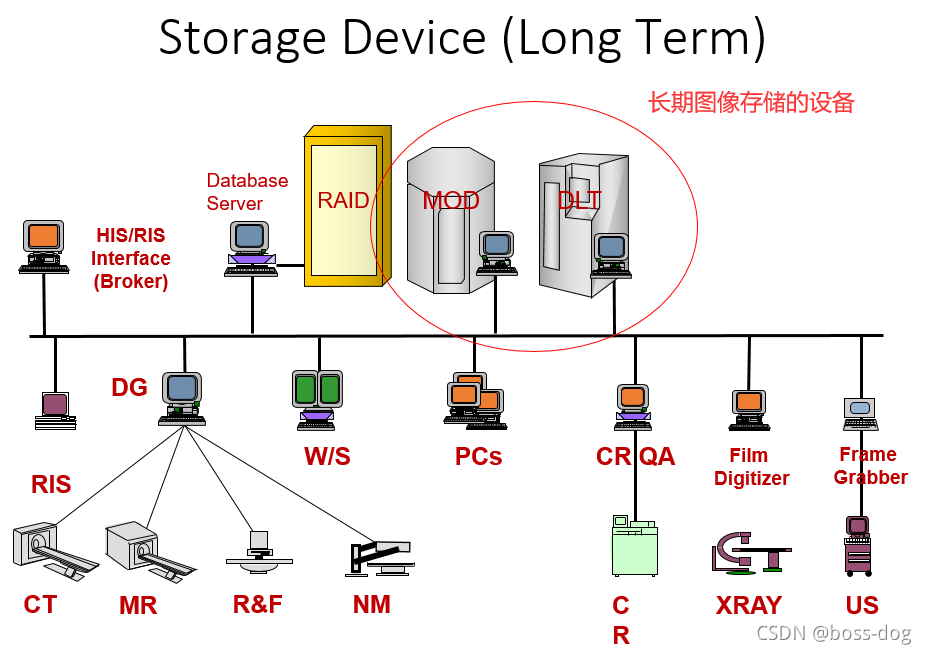

- PACS系统的组成:

HIS/ RIS(关于病人的信息、预约信息)

Broker(代理)

ePR gateway(网关)

Database Server(数据库)

Image Server (RAID)(图像数据库)

Long Term/ Near line Archive(长期、近期的档案整理)

Networks(网络)

Digitizer(数字化处理)

Acquisition Gateways(采集网关)

Non-DICOM modality gateway(非DICOM格式图像的处理)

DICOM Print Server(需要连接胶片打印机)

Media Server(拷刻成光盘)

Reporting Server(形成意见报告)

Monitor QC Server(和显示器的连接)

Web Server(Web服务端)

Workstations(给医生看图片的工作站)